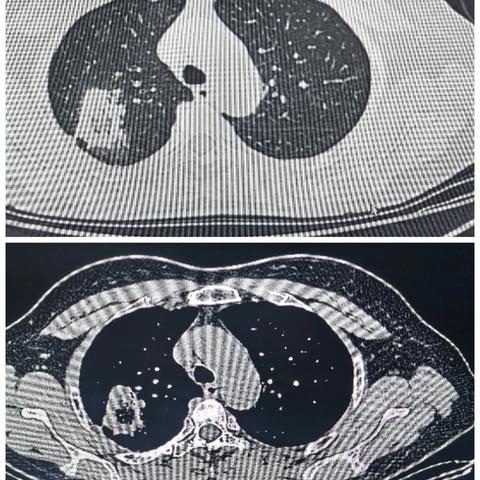

精准狙击:年轻肺结节患者的微创治疗之路

2025-03-16 796阅读

从DeepSeek到AI肺结节筛查软件:革新肺癌早期诊断

2025-03-03 906阅读

射频残留危害大,外科手术解烦忧——射频消融后外科手术治疗

2025-02-24 1710阅读